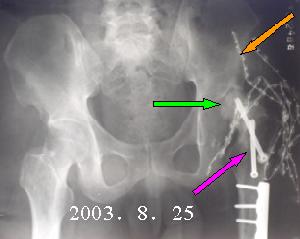

X線檢查 臨床檢查是診斷的第一步,它只能說明髖關節有問題,但最後作出診斷需用X線攝片。嬰兒出生後2~3月內,股骨頭骨骺骨化中心尚未出現,X線檢查乃依靠股骨頸的乾近側端與髖臼關係來測量。骨化中心出現後,攝片包括雙側髖關節的骨盆片可以確定診斷,攝片時將雙下肢併攏,將患肢上推和下拉住各攝一片對比測量,則變化更明顯可靠。測量方法有以下幾種:

(一)連線雙側髖臼Y型軟骨的水平線(稱Y線或Hilgenreiner線),自髖緣外側骨化邊緣的垂線(稱Perkin線或Ombredarne線),兩線交叉將髖臼劃為四區,正常股骨頭骨化中心應在其內下區,若位於其它地區,則為脫位。脫位側骨化中心常較小。

YY′=Y線Hilgenreiner線;EP、E′P′=Perkin線;虛線=Shenton線(健側相連續)

(五)興登(Shenton)線 正常骨盆X線中恥骨下緣之弧形線與股骨頸內側之弧形可以連成一條完整的弧度稱做興登氏線。凡有髖脫位,半脫位病例中,此線完整性消失。

此線在任何脫位中都消失,因此不能區別炎症、外傷、先天性等情況。但是仍不失為最簡單的診斷方法這一。

在有條件時可套用CT或MRI檢查便可明確診斷。